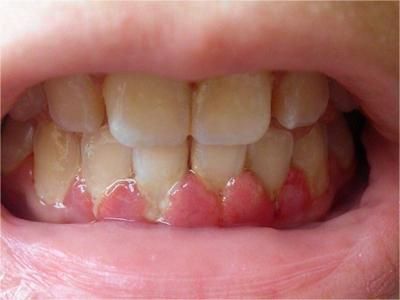

牙龈炎是发生于牙龈组织的炎症,患者可出现牙龈出血伴肿胀、发红、正常形态改变和偶尔不适等症状。本病主要由口腔卫生状况差导致,包括口腔不洁、牙菌斑等,诊断依据临床检查,治疗包括专业牙齿清洁和加强家庭口腔卫生。

牙龈炎可先引起牙齿与牙龈之间的沟(龈沟)加深,然后牙龈充血,炎症围绕一个或多个牙齿,伴牙龈乳头肿胀和易出血。一般无痛,可自行消退,也可维持轻度炎症数年。